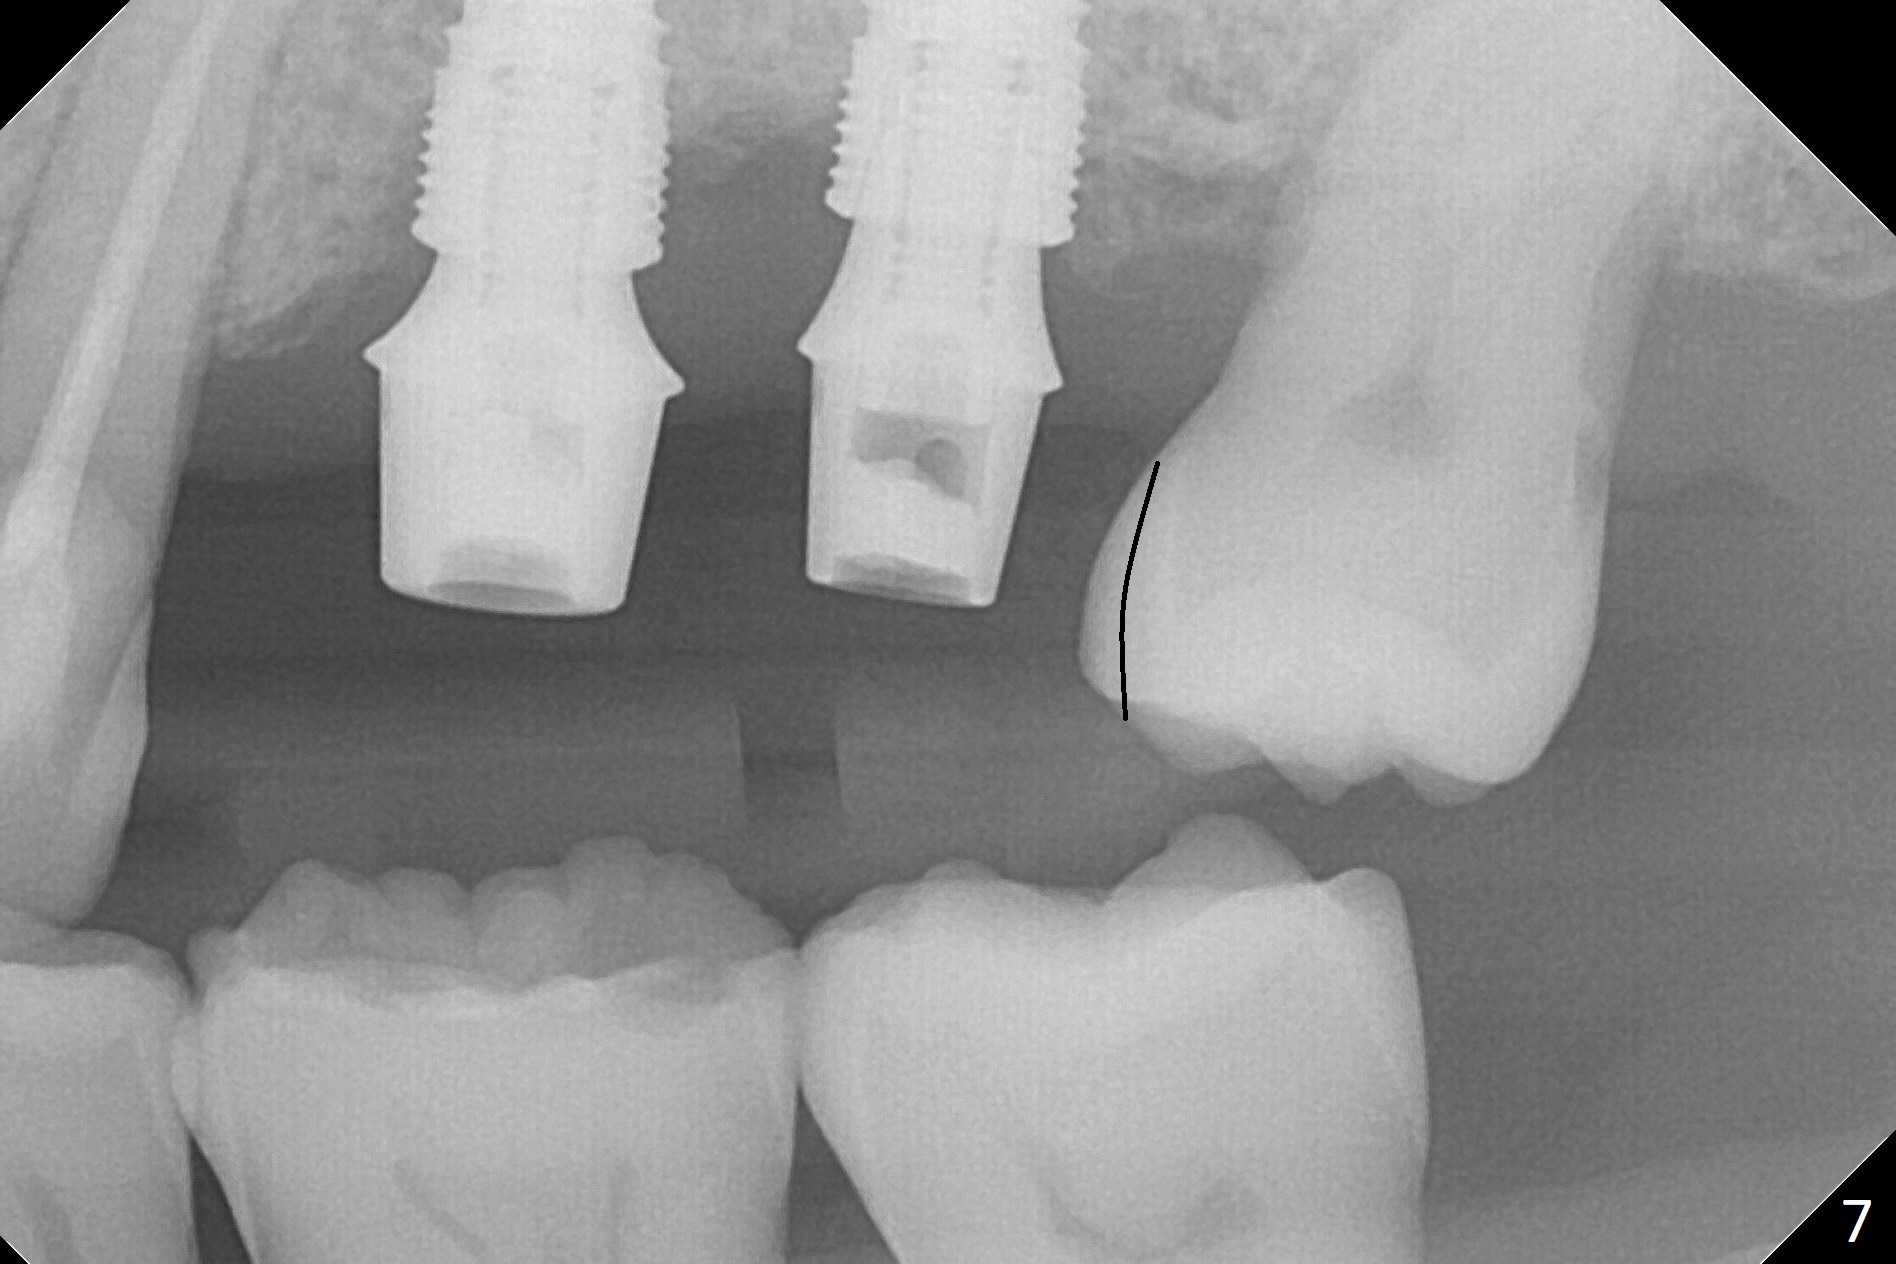

When 1.2 mm drill is used for osteotomy at #14 and 15, the bone feels to be soft (Fig.1). After change in trajectory (Fig.2), Expander 1 (Fig.3: E1, 1/1.6 mm) can be inserted at #14 and 15, while E2 (1.2/2.3 mm) cannot at full length at #14, suggesting hard bone. Osteotomy continues with drills until 4.1x14 mm, followed by insertion of E4 (2.4/3.7 mm) at #14, while osteotomy goes on until E3 (1.7/3.1 mm) at #15 (Fig.4). A 4.5x12 mm SM implant is placed with 50 Ncm (with insertion of a 5.8x4(2) mm abutment as a guide for #15 osteotomy, Fig.5). The apical portion of the osteotomy at #15 (Fig.5 red line) is finished with drills, leading to placement of a 4.5x12 mm implant (>50 Ncm) and 4.8x4(2) mm abutment (Fig.6). With bone density is more than 200 units, bone expansion appears to be not indicated. The patient returns for #13-15 crown prep 4.5 months postop (Fig.7). Abutments change to 5.8x5(3) and 5.8x4(3) mm at #14 and 15, respectively with mesial reduction of the tooth #16 (curved line) before impression. Minimal bone loss is observed 1 year 5 month post cementation (Fig.8,9), thanks to pre-existing wide bone.